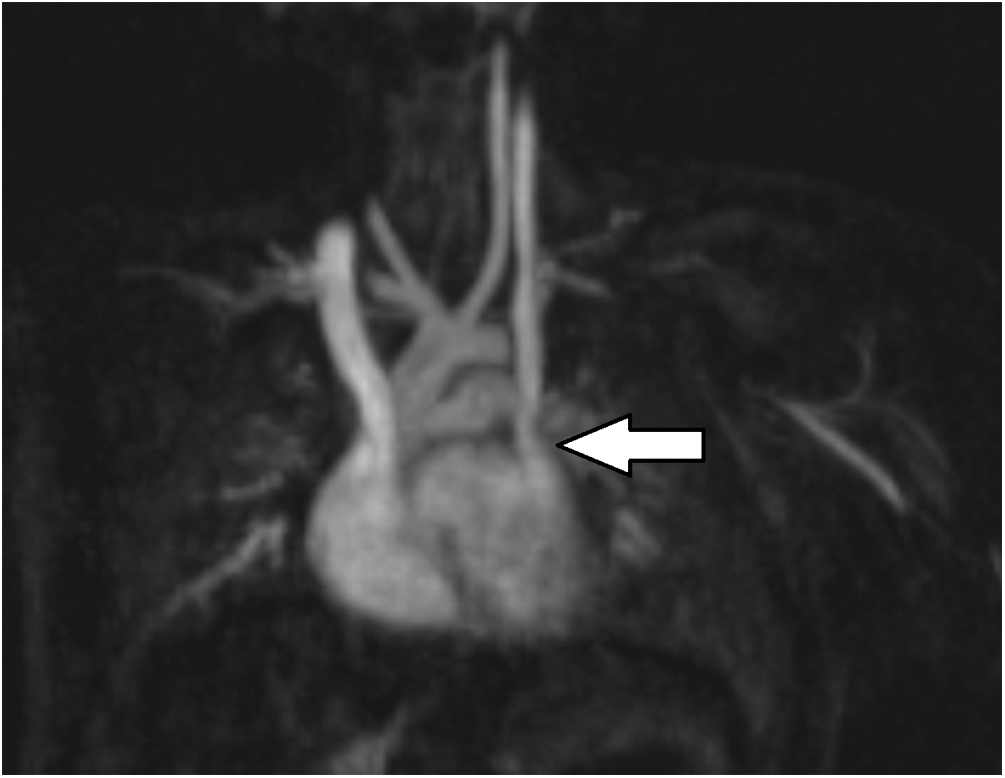

After discharge, further progression in ventilator weans was limited by persistent episodic hypoxemia at home. Over time, the patient’s parents noted a pattern of reproducible cyanosis with head turn to the right, which they demonstrated for providers at a follow up appointment in pulmonary clinic when the patient was 24 months old. The positional hypoxemia was not associated with hypoventilation (no changes in end-tidal CO2 or exhaled tidal volumes) and was not responsive to supplemental oxygen, but improved with return of head to neutral position, raising concern for a position-dependent shunt. Review of past echocardiograms suggested a possible PLSVC in the absence of a dilated coronary sinus. Saline contrast echocardiography with injection in the left arm showed vigorous contrast return to the left atrium, suggestive of a PLSVC to left atrial connection (Fig. 1). This was further confirmed on cardiac MRI for surgical planning, demonstrating a PLSVC draining into the left atrium with a small bridging vein between the right and left superior vena cavae. With the patient’s head turned to the right, there was a 50% decrease in flow in the right SVC and a compensatory increase in flow in the left SVC (Fig. 2).

Figure 2: Oblique coronal maximum intensity projection image from a cardiac MR angiogram showing normal right SVC and a PLSVC draining to the left atrium (arrow)